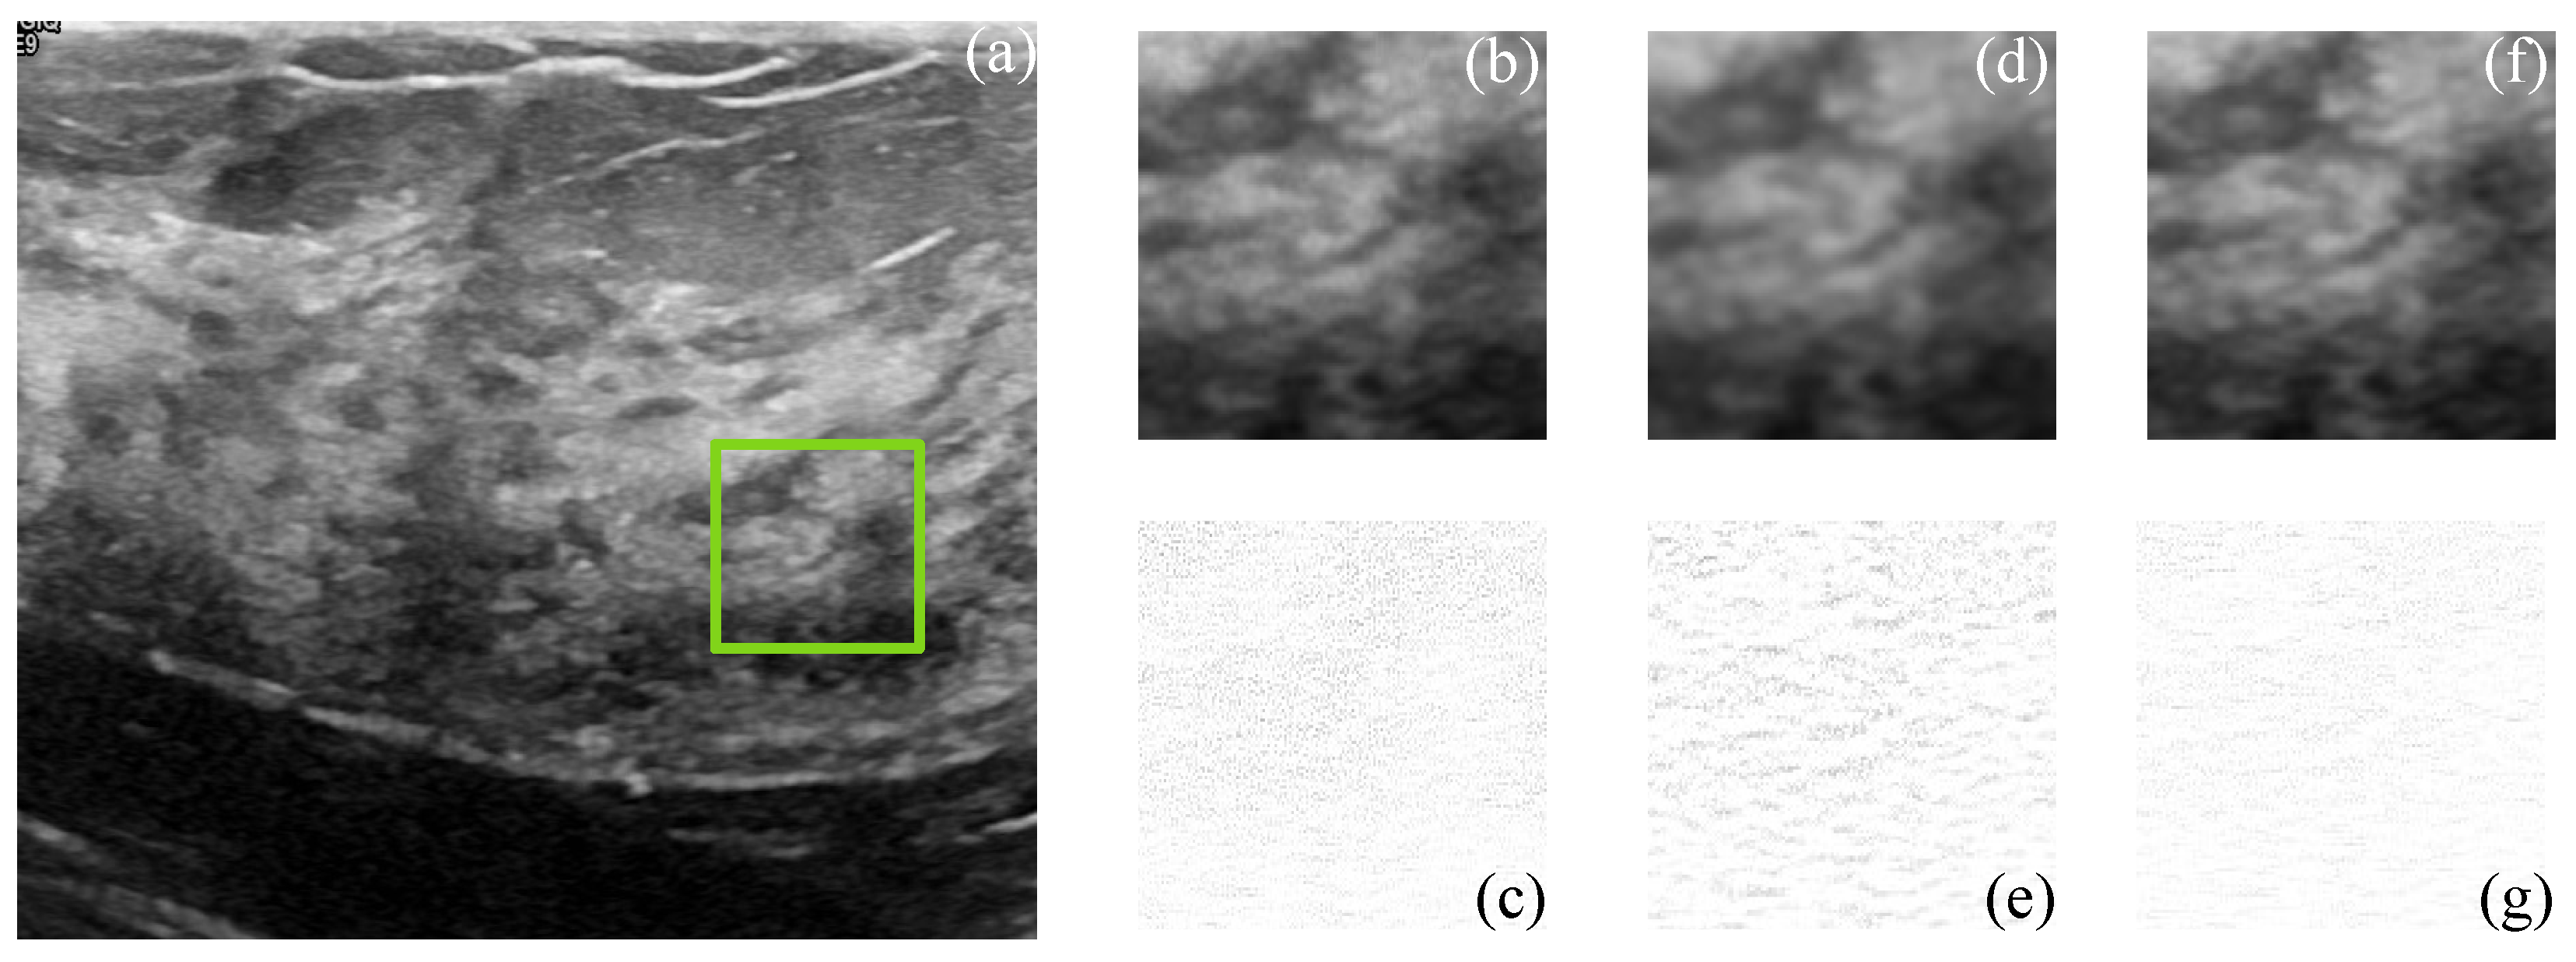

Figure 5 and Figure 6 show the simulated and filtered ultrasound images, indicated as US-sim-04 and US-sim-11, respectively, with the subjective visual comparison with the BM3D and SD-BM3D.

The visual results in Figure 5 and Figure 6 show that the designed framework can achieve good performance for the despeckling procedure. As can be observed, the BM3D technique produces artifacts that degrade the processed images, and the SD-BM3D method tends to over-smooth edges and fine details by comparing the error images. The principal disadvantage of these techniques is that they do not consider the images’ local statistical properties and texture features for grouping the 3D blocks, which limits the denoising performance. The proposed CMI-3DSVD filter outperforms the mentioned denoising methods by preserving important details of the image, such as edges, and by not blurring homogeneous regions.

Figure 5. Subjective visual results of the despeckled simulated US image US-sim-04. (a) Input image. Details are taken from the region marked in green: BM3D: (b) despeckled image, PSNR = 15.47 dB, EPI = 0.2791; (c) error image. SD-BM3D: (d) despeckled image, PSNR = 16.07 dB, EPI = 0.2898; (e) error image. CMI-3DSVD: (f) despeckled image, PSNR = 16.35 dB, EPI = 0.3156; (g) error image.